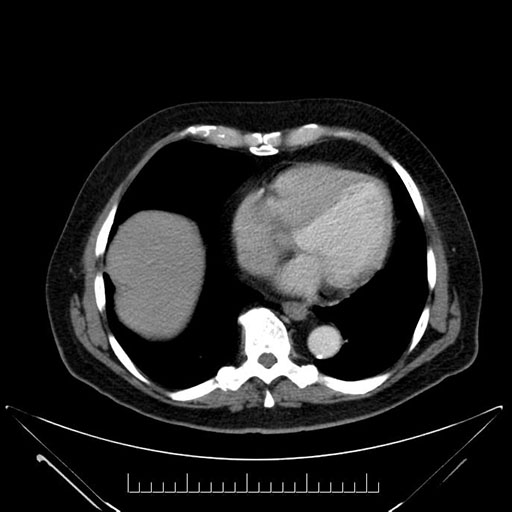

Imaging Analysis

Look through the patient's CT scan to identify any areas of concern for the necessary procedure.

Based on your CT findings, which issue(s) would give reason for "planned slowing down moment(s)" in this case?